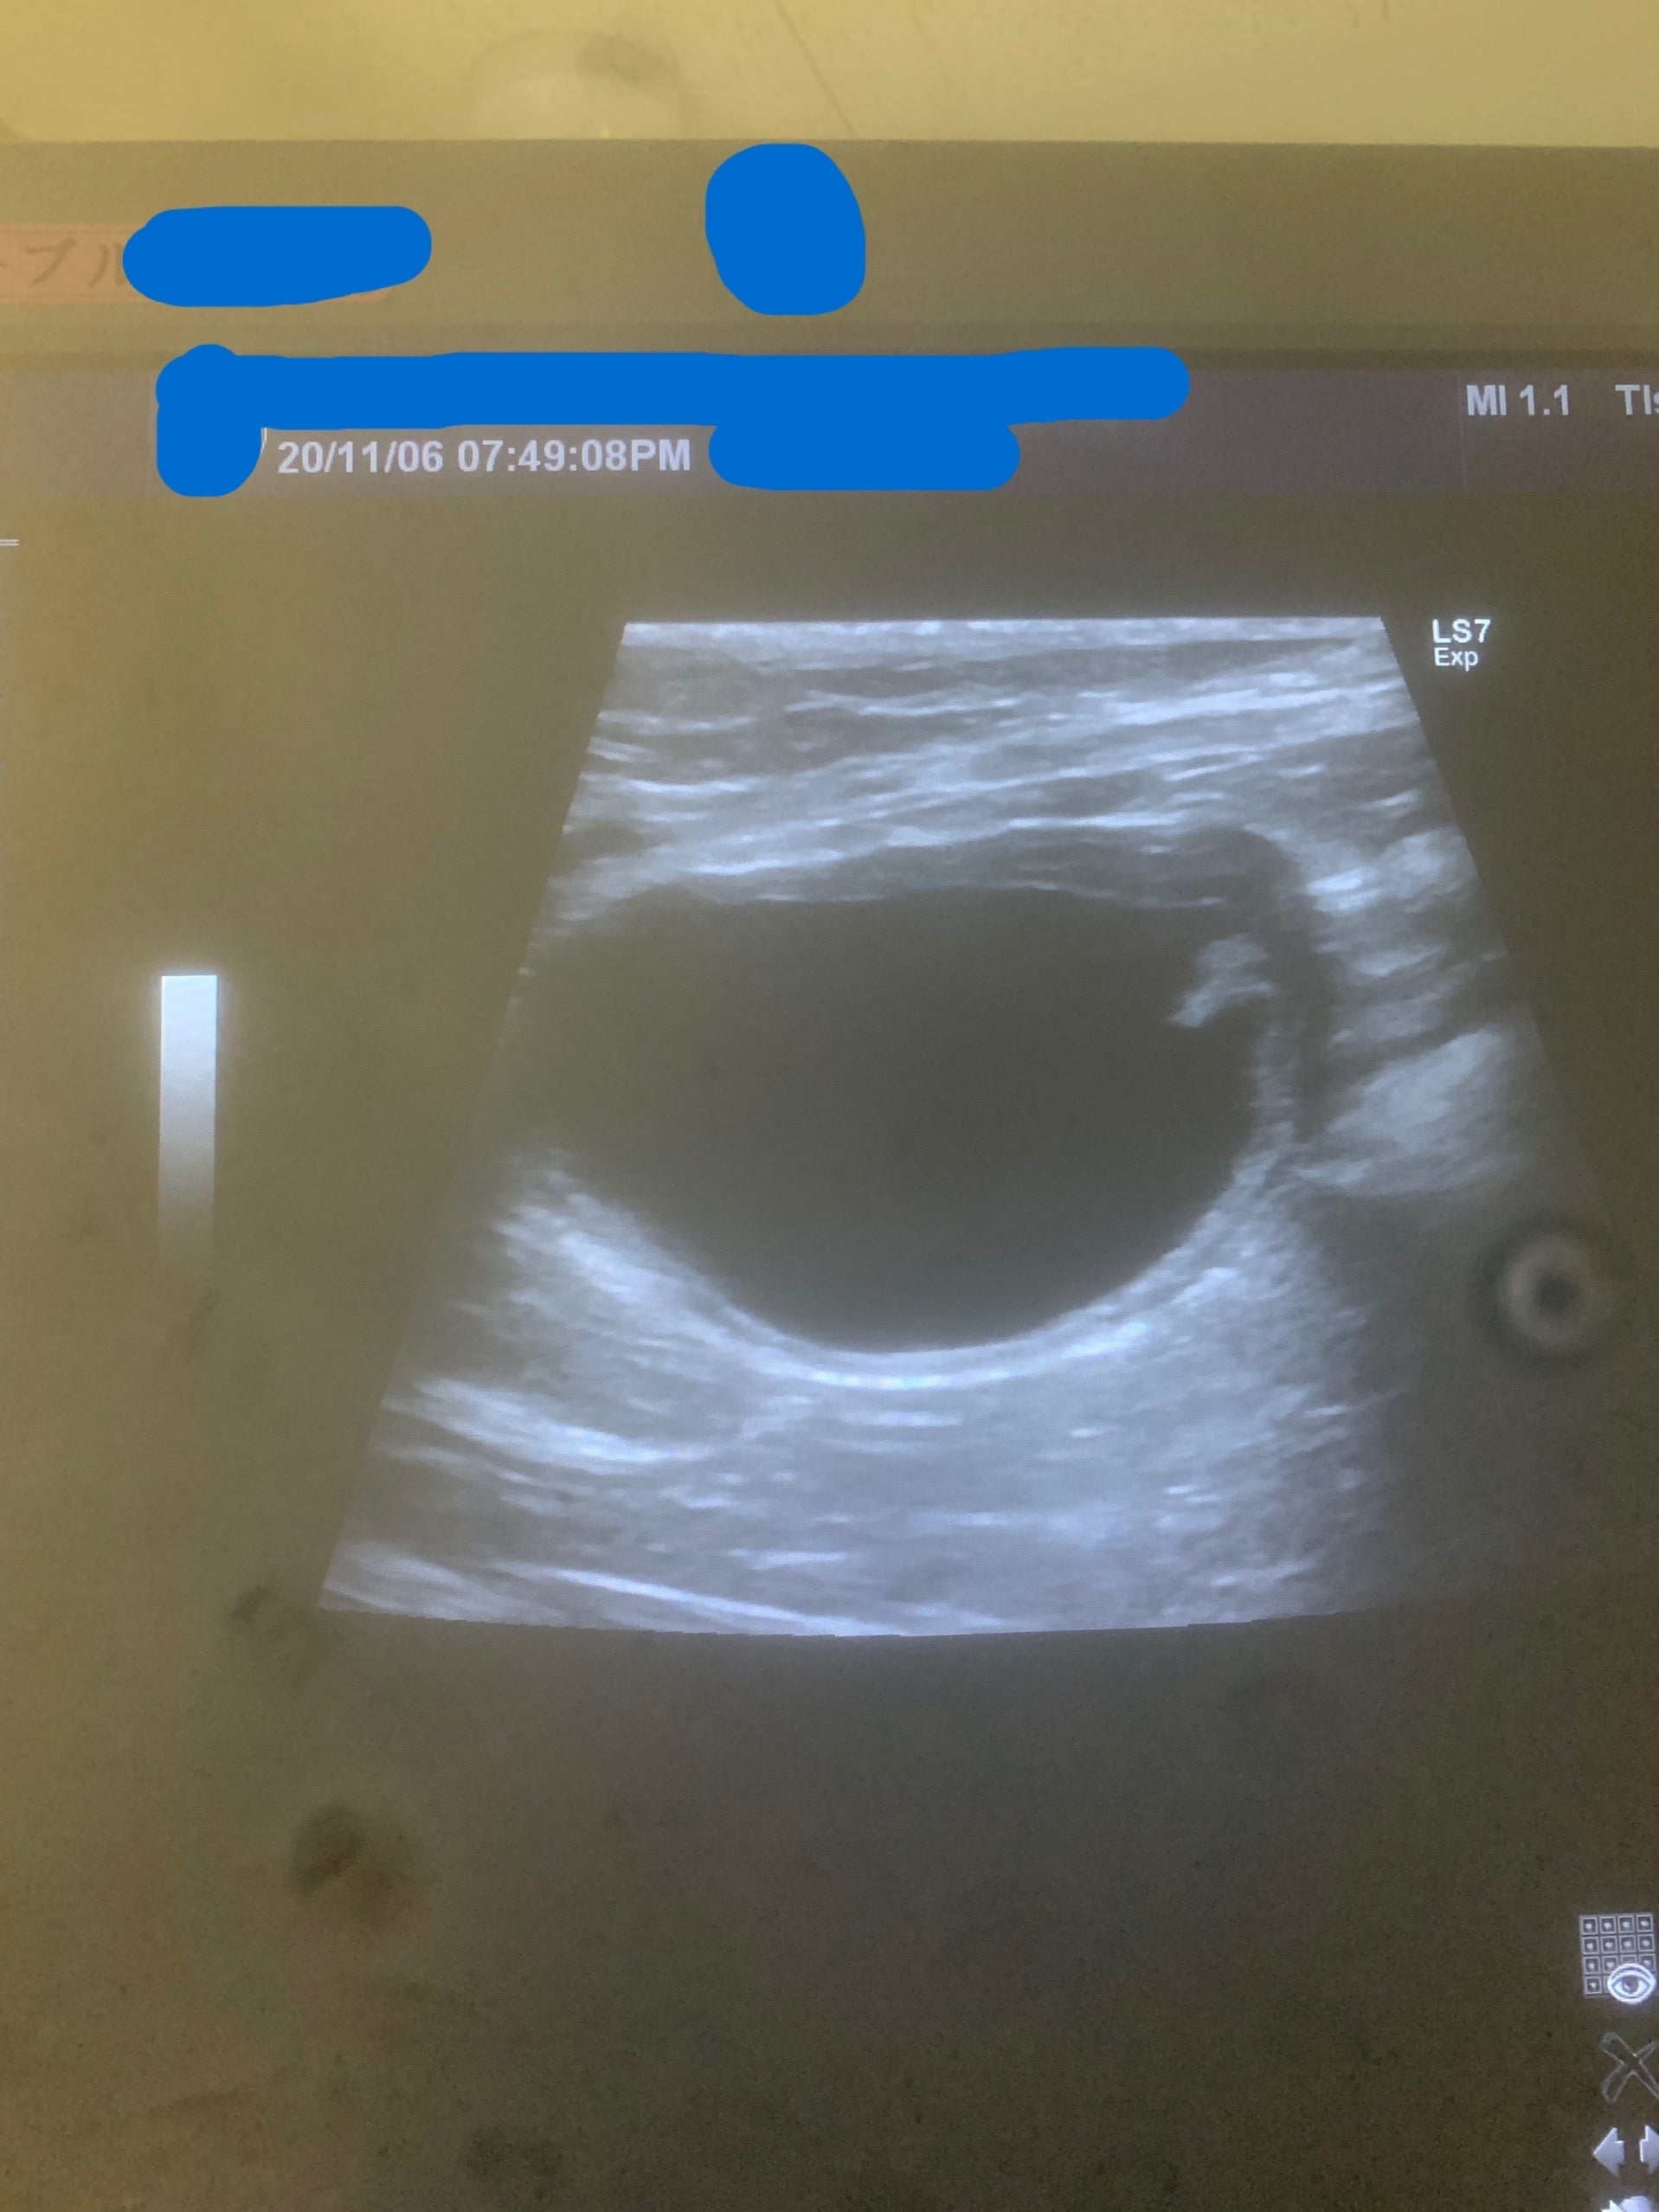

【11月6日撮影のエコー】

塊はなくなって、

膀胱の腫れも収まっています。